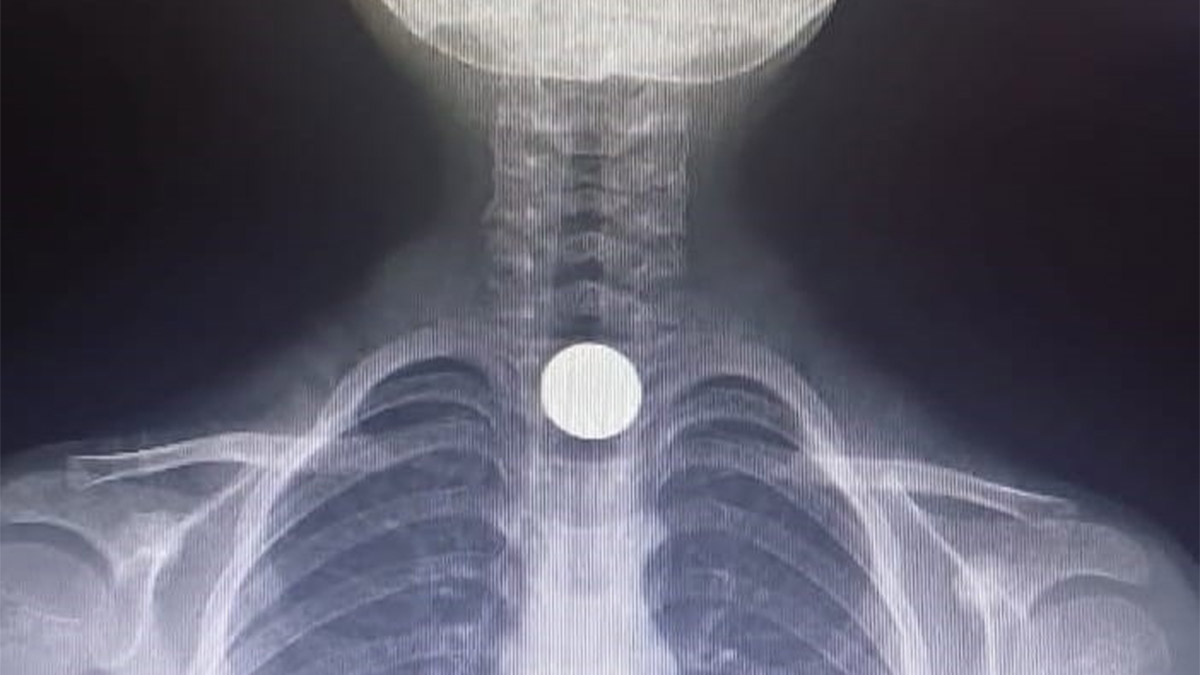

Korkutan olay, Mesudiye Mahallesi Sarmaşık Sokak’taki bir apartmanda meydana geldi. Evinde oynayan 5 yaşındaki Yusuf Z., halının üzerinde bulduğu 50 kuruşluk madeni parayı ağzına götürdü. Parayı yutan Yusuf, bir anda fenalaştı. Durumu fark eden aile, çocuğu İnegöl Devlet Hastanesi’ne götürdü. Hastanede doktorlar tarafından yapılan tetkiklerde paranın yemek borusuna takıldığı tespit edildi. Çocuk, boğazındaki paranın çıkarılması için Bursa Yüksek İhtisas Eğitim ve Araştırma Hastanesi’ne sevk edildi.